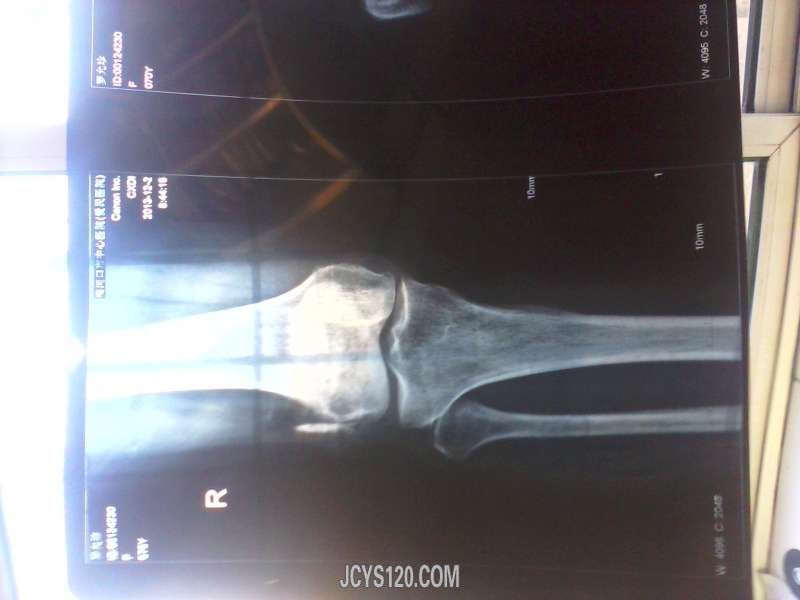

• 患者女,57岁,腰腿疼痛一年,伴双下肢水肿一个月【左腿水肿重,右腿轻】,曾口服双氯芬酸钠肠溶片,壮腰健肾丸,vb1治疗,因不明水肿是怎么回事,于是推荐到市级医院检查,经做CT,腰椎4节突出0.1,医院诊断腰间盘 ...  阅读全文>